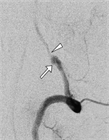

1. 急性期の血管内治療について、解離による頭蓋外頸動脈狭窄とそこからの塞栓による頭蓋内動脈閉塞については血栓回収療法の有用性が示されてきている。

1. MRA、CTAによって解離の特徴的な所見を見逃さないようにする。